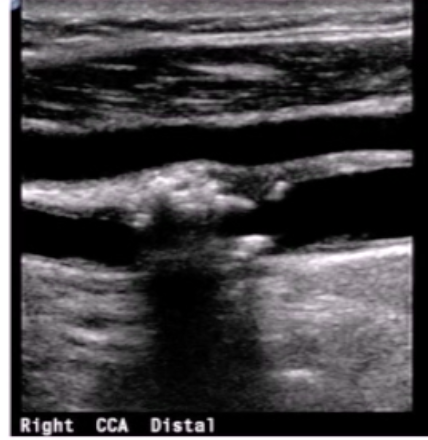

Where should CCA velocity ideally be measured?

a few cm proximal to carotid bifurcation